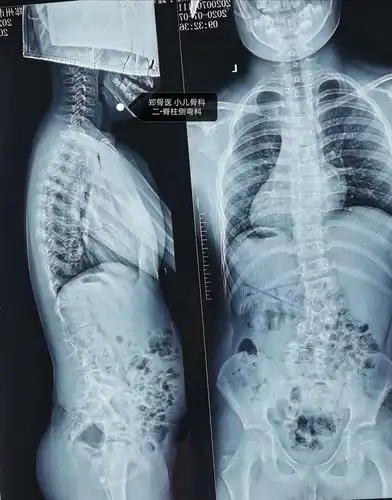

郑骨医,小儿骨科二脊柱侧弯科短阶段固定治疗脊柱侧弯一例

患者,女性,12岁8个月,发现脊柱弯曲4年,最近又加重趋势.